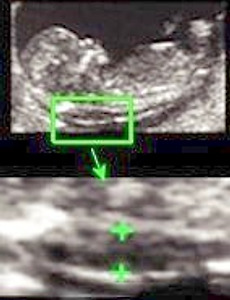

nt,nuchal translucency What is the Nuchal Translucency? The nuchal translucency (also spelled nucal translucency) is a collection of fluid beneath the fetal skin in the region of the fetal neck and this is present and seen in all fetuses in early pregnancy. The fluid collection is however increased in many fetuses with Down's syndrome and many other chromosomal abnormalities. It is called a 'translucency' because on u.. 2013. 10. 16. 이전 1 2 3 4 다음